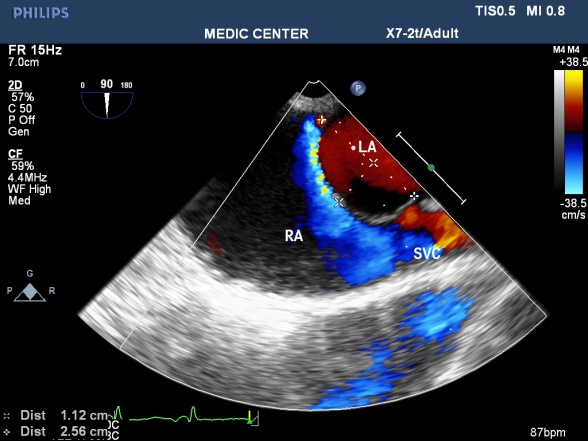

Atrial Septum Aneurysm: Atrial septum with redundant tissue bulging over 10mm into the right or left atrium or both atria in a heart circle creates atrial septal aneurysm. It is found in about 1 % [23] of consecutive autopsies and 4.9% of patients performed TEE for other reasons than indication for sources of emboli [24]. ASA is often associated with PFO, according to Schneider the rate is 77% [25], according to Silver & Dorsey the rate is 50% [26]. Data from Andreas M showed 54.4% shunt through atrial septum in patients with ASA [27]. Mechanisms of cardiogenic embolism consist of direct embolism from thrombus formation in aneurysm, paradoxal embolism through PFO or ASD from venous sources and stagnation of blood in aneurysm with poor contraction in atrial fibrillation [28]. We have a case stroke with atrial septal aneurysm associated with PFO detected by TEE (Figures 16-19).

Figure 16. Sizing ASA by 2D TEE; “TEE image from Nguyen Tuan Vu”

Figure 19. ASA with L-R shunt through PFO; “Image performed by Nguyen Tuan Vu”

Patent Foramen Ovale (PFO)

Our data showed 10 cases of PFO including 9 cases of PFO and a case coexistence of the two conditions (PFO and ASA) (Figure 20).

Figure 20. PFO with small L-R shunt; “TEE image performed by Nguyen Tuan Vu”